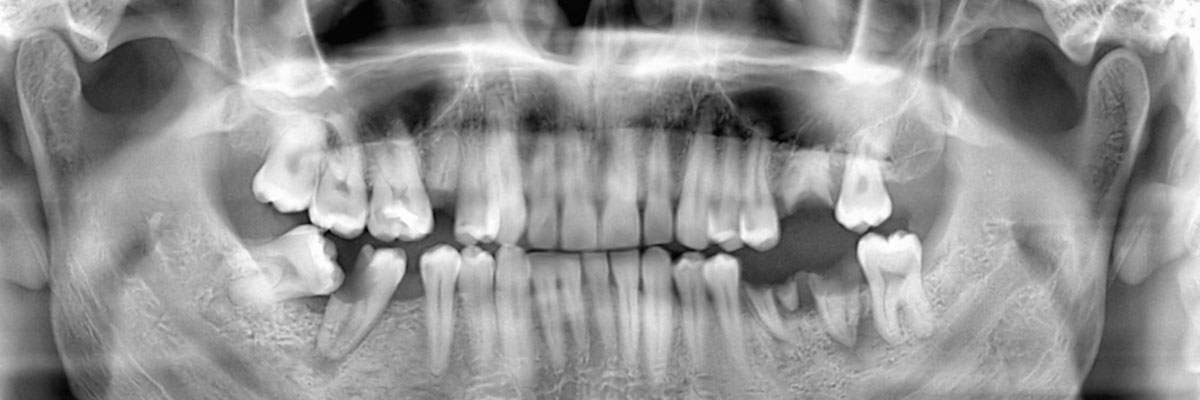

You may need a wisdom teeth extraction at some point in your life. It is rare for a person to have enough room for all of their wisdom teeth, and as a result, they tend to grow in impacted. This can be uncomfortable, push your other teeth forward, and create a space for food to become trapped; it can also increase your risk of infection and decay. This is why we often recommend that our patients have their wisdom teeth removed. When you schedule an appointment with Golden Dental Group, we can examine you, take X-rays, and let you know if and when you should schedule an extraction procedure. You can reach us by calling (281) 693-3330.

This is a dental procedure where your wisdom teeth are removed. How they are removed will be based on their current location and whether or not they are impacted.

If your wisdom teeth have grown in straight, removing them is fairly easy. In this case, you would visit a dentist to have them pulled out using dental tools. Most likely, no surgery would be required. However, if your teeth are impacted, the procedure requires oral surgery. In order to access the actual tooth, the gum tissue covering it will need to be cut open. After numbing the area, a flap will be created in the gum tissue. This allows the dentist or oral surgeon to view the tooth. If muscle or bone is covering it, that will also need to be cut away to provide clear access to the actual tooth. At this point, your dentist may be able to grab the tooth and simply lift it out of the socket. If, however, it does not budge when being wiggled, then the actual tooth will need to be broken into several pieces that can be extracted individually.

At Golden Dental Group, we understand that each of our patients is unique and so are their teeth. Whether or not you need to have your wisdom teeth removed by a dentist, will really depend on the size of your palate. If you have plenty of room for all of your teeth and your third molars, they can stay in place. There is no point in removing something that grows in straight and is healthy. However, any tooth that grows in impacted needs to be removed because it is posing a direct threat to your other teeth and roots in addition to being a target for infections. The best way to find out if your wisdom teeth should be removed is to call 281-693-3330 and schedule an appointment with our Katy dentist office. We can make a recommendation and answer any other questions you have about the procedure itself.